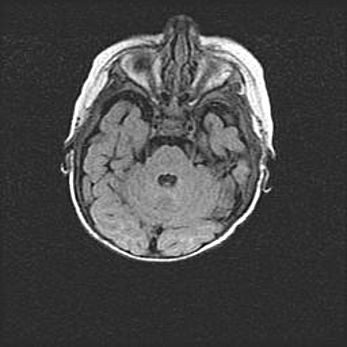

Мальформация Денди-Уокера. Киста задней черепной ямки.

Агенезия мозолистого тела.

Возраст: 2,5 месяца

Вес: 2420 г

Пол: женский

Окружность головы: 37 см

Срок гестации: 32 недели

Мальформация Денди—Уокера — редкий вид патологии ЦНС, представляющий собой врожденный порок развития каудального отдела ствола и червя мозжечка, ведущий к неполному раскрытию срединной (Мажанди) и латеральных (Лушка) апертур IV желудочка мозга. Для этогно синдрома характерна триада симптомов: гипотрофия червя мозжечка и/или полушарий мозжечка, кисты задней черепной ямки, гидроцефалия различной степени. В 70% случаев порок сочетается и с другими аномалиями головного мозга, в частности с агенезией мозолистого тела.